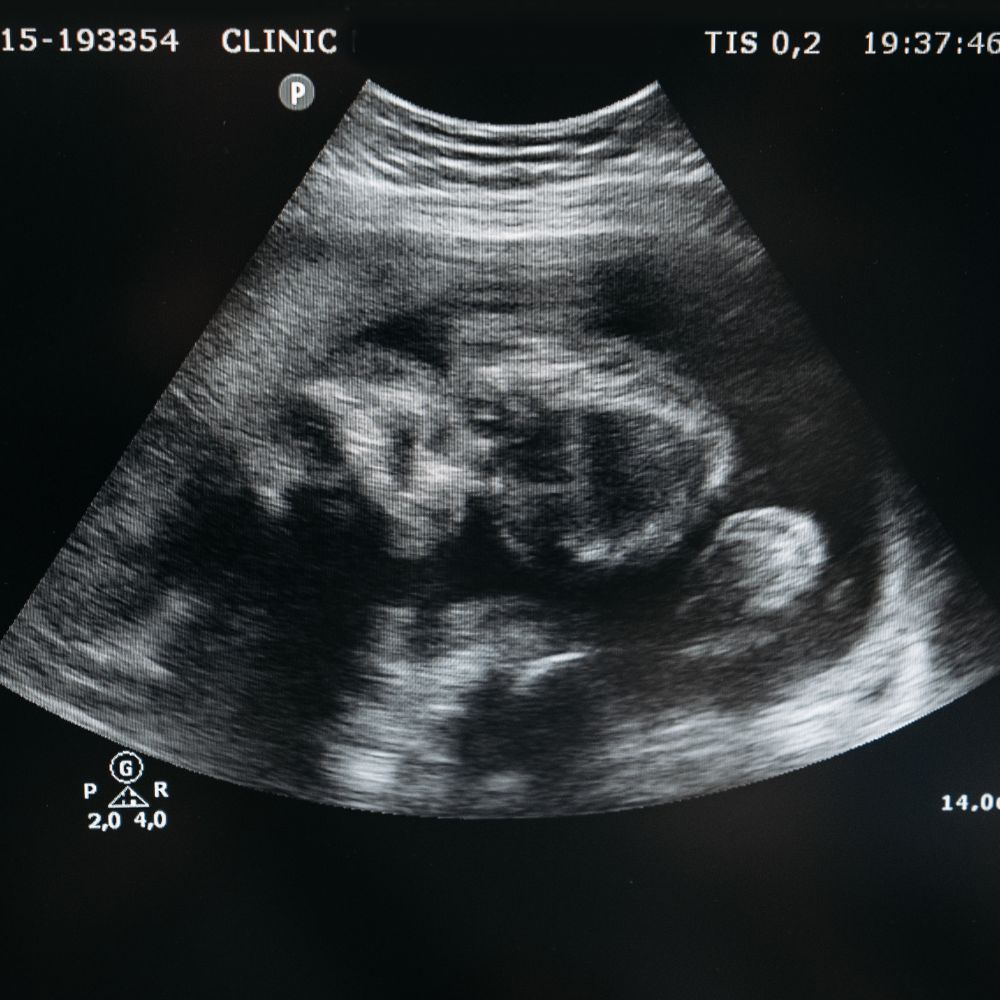

4-2. 병원 검진 시기

테스트기로 양성 반응이 나왔다면, 산부인과를 방문하여 정확한 진단을 받는 것이 좋습니다. 보통 마지막 생리 시작일로부터 5-6주가 지나면 초음파로 임신낭을 확인할 수 있고, 6-7주가 되면 태아의 심장 박동을 확인할 수 있습니다.